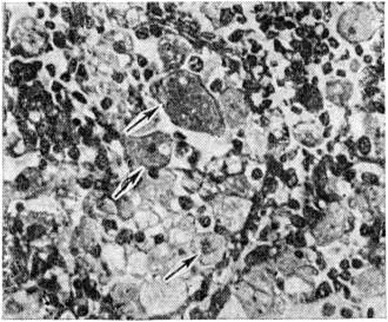

Патологическая анатомия. На вскрытии обнаруживают резкое увеличение размеров печени, селезёнки, лимфатических узлов, надпочечников с окрашиванием их ткани в жёлтый цвет. Иногда отмечается депигментация или желтовато-коричневое окрашивание кожи. Гистологически в тканях внутренних органов выявляются крупные (диаметром 30—60 микрометров), овальной формы макрофаги — так называемый клетки Пика. Они содержат от одного до четырёх ядер, цитоплазма их пенистая за счёт накопления мелких капель сфингомиелина (рисунок). Клетки Пика хорошо окрашиваются суданом III, осмием, нильблаусульфатом и другими красителями, дают положительную реакцию Смита — Дитриха, окрашиваясь в черно-синий цвет. Большое количество клеток Пика обнаруживают в печени; они представлены звездчатыми ретикулоэндотелиоцитами (купферовскими клетками), увеличенными в размерах, цитоплазма их заполнена каплями жира. В селезёнке лимфатических, фолликулы не определяются, пульпа её диффузно инфильтрирована клетками Пика, встречаются кровоизлияния, зоны некроза на различных стадиях организации, участки рубцевания. В надпочечниках скопления клеток Пика обнаруживают главным образом в мозговом слое. В почках клетки Пика встречаются редко, в нефротелии выражена жировая дистрофия.